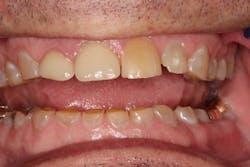

CHRIS CAME TO MY OFFICE IN AUGUST 2013, after another dental professional told him that he needed dentures. He realized that his teeth were wearing away, and he did not want to lose any more tooth structure (figure 1).

Figure 1: Before